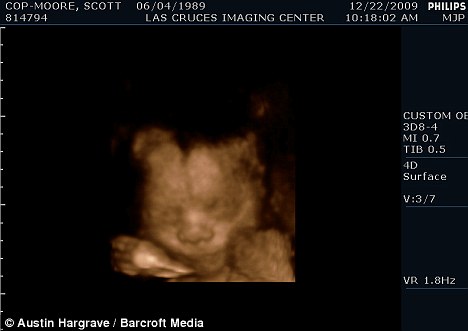

掃描顯示斯科特懷的是個(gè)男孩

現(xiàn)年30歲的斯科特·穆爾和丈夫托馬斯來自美國加利福尼亞州,兩人原先都是女性,托馬斯接受過變性手術(shù)后成為真正的男子漢,斯科特仍然留有一些女性器官并持有女性出生證明,所以他們的婚姻是合法的。目前他們已經(jīng)知道未出生的孩子是個(gè)男孩,準(zhǔn)備給他取名“邁爾斯”。

2009年6月,斯科特從一名男性朋友那里取得精子,并通過人工受精成功懷孕。他打算在當(dāng)?shù)氐尼t(yī)院自然分娩。